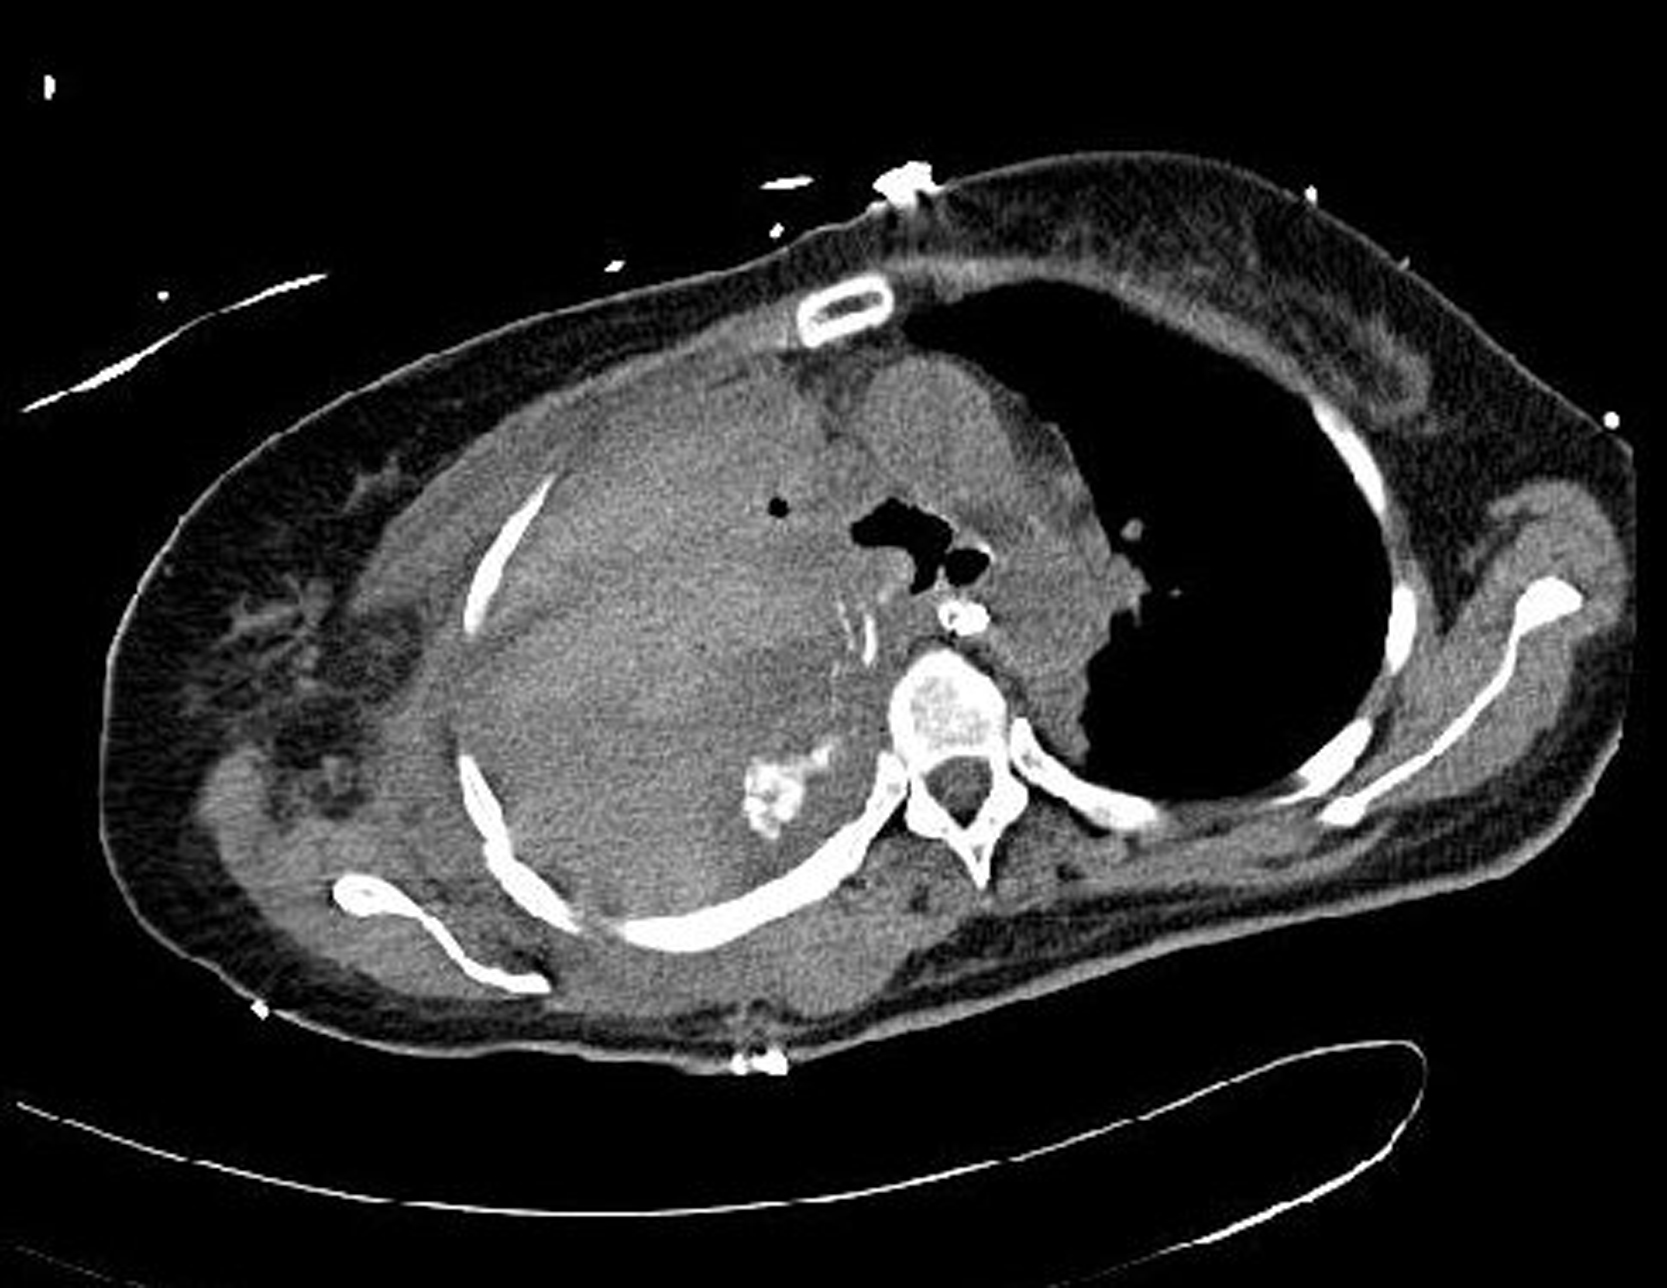

Postoperatively the patient did well except she developed a deep venous thrombosis of the right upper extremity, which was treated accordingly. The air leak and infection appeared to be resolved. Repeated chest CT scans showed a good filling of vascularized soft tissue to the right middle and lower chest ( Fig. 24.6 ). The right chest wound repair site remained closed. She was discharged from the hospital 2 months later.